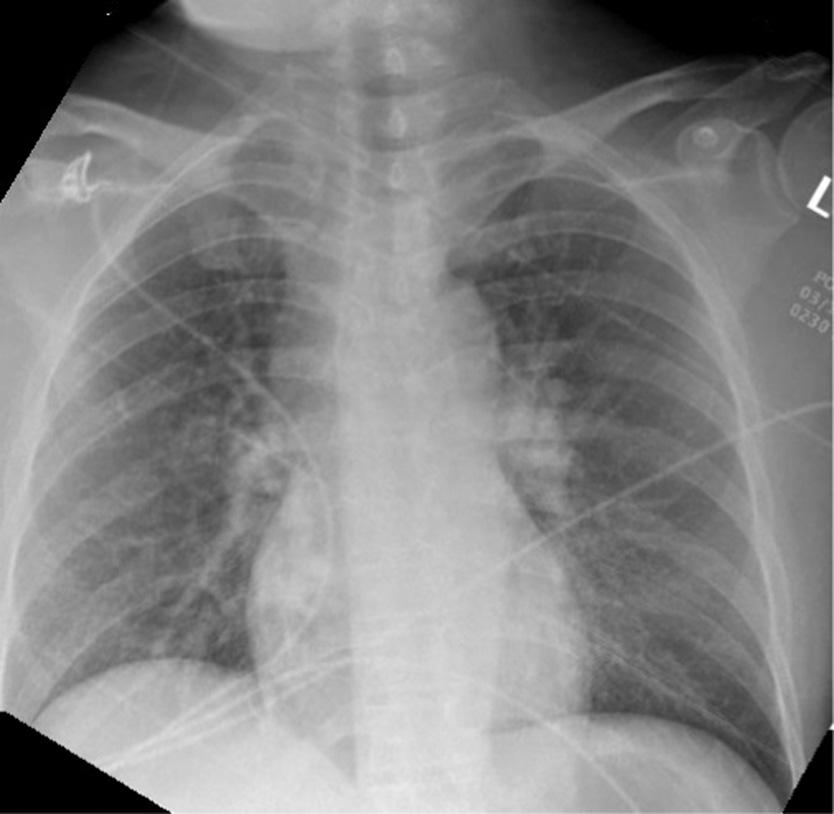

Thepatientwasplacedon100%oxygenvianonrebreathermaskandtransportedtoalocalemergency department(ED).UponarrivalattheEDhedeniednew complaints,andhisvitalsandphysicalexamwerenot significantlychanged.Hiselectrocardiogram(ECG)showed anatrialsensedpacedrhythmconsistentwithpriorECGs. Hehadachestradiograph(CXR)showingleft fifthandsixth ribfractureswithamoderatecircumferentialpneumothorax (Images2 and 3).

Image2. Chestradiographwitharrowspointingtoleft-sidedmoderatecircumferentialpneumothorax.Thereisalossofsymmetry,avisible lungborder,andlossoflungmarkingsuperiortothelungborder.